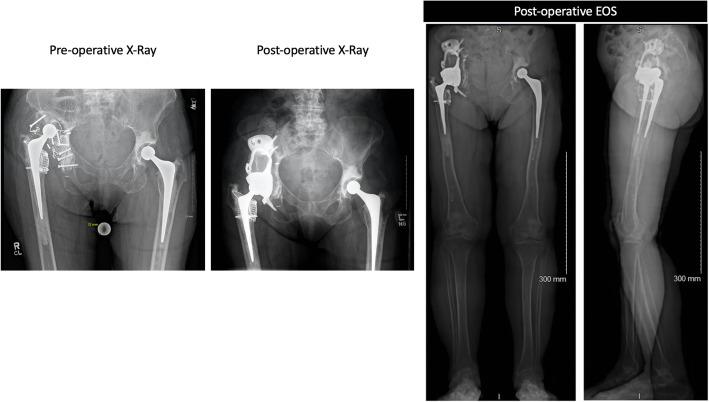

This was a prospective case study of 25 patients. We report the analysis of pre-operative LL status and planned LL restoration measured on CT, in relation to the achieved LL measured post-operatively in functional, weight bearing position. Our primary objective was the assessment of restoration of CoR as well as the anatomical and functional LL using biplanar full-length standing low-dose radiographs; our secondary objective was to evaluate the clinical outcome.

这是一项对25例患者的前瞻性病例研究。我们报告了术前下肢长度状态分析以及在CT上测量的计划下肢长度恢复情况,并与术后在功能负重位测量的实际下肢长度相关。我们的主要目标是使用双平面全长站立低剂量X线片评估旋转中心的恢复以及解剖学和功能性下肢长度;次要目标是评估临床结果。